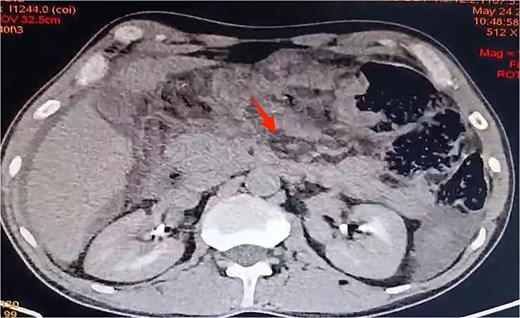

A contrast-enhanced abdominal CT showed Balthazar E pancreatitis with peripancreatic necrosis, thickening of the transverse colon and first jejunal loop, and sealed colonic perforation. Perisplenic and perihepatic fluid collections were noted, with no free air (Figs 1 and 2).

Axial view of contrast-enhanced abdominal CT scan revealing transverse colon wall thickening and a sealed transverse colon perforation.